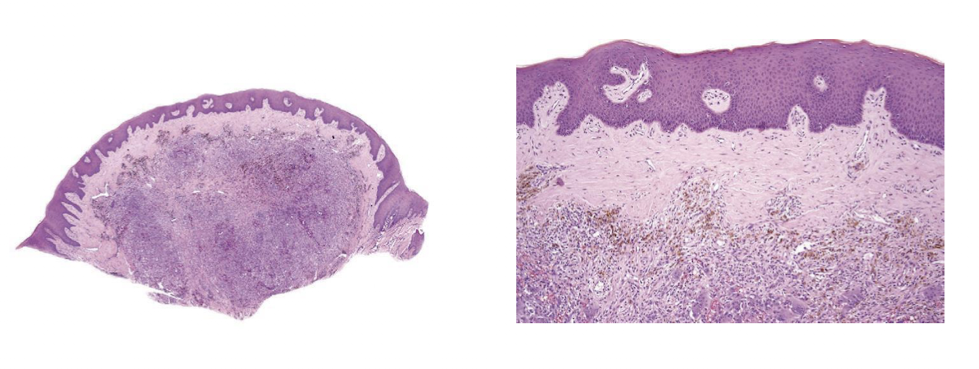

medication-induced pigmented lesion

pt also has pigmented lesions in vestibule, on palate, tori, etc

medication-induced pigmented lesion can appear on skin

amalgam tattoo

antimalaria for immune related purposes, milatinab or quinone

no scarring unlike amalgam tattoo

bluestain = iron, medication-induced pigmented lesion